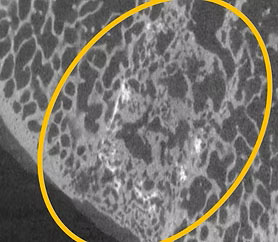

微CT扫描

Micro CT scan

4.5个月时的CoreTlage植入部位

植入体已很好地融入移植部位